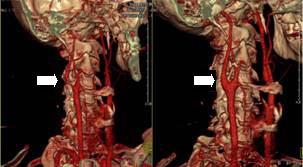

周大伯今年55岁,杭州市某单位公务员,有高血压病10多年,平时长期吸烟喝酒。最近1个月来老周出现陈发性右眼看不见,时间很短,就几秒钟。一开始以为身体劳累所致,没有特别在意。但最近2周以来,发作越来越频繁,而且持续时间越来越长。老周以为是眼睛有问题,来我院眼科检查。眼科的沈洁主任仔细检查后排除了眼睛本身的问题,怀疑是颈动脉的病变引起,果真颈动脉B超检查结果证实老周的双侧颈部大血管都有病变,特别是右侧的颈动脉由于动脉粥样硬化斑块而严重狭窄(狭窄率达到82%),几乎处于闭塞的边缘。幸运的老周转到神经外科就诊。负责诊治的是神经外科的孙伟军副主任医师,判断老周的症状是典型的视网膜型短暂性脑缺血发作(TIA),入院后老周接受了一系列更针对性的检查,进一步明确病情并评估手术风险,包括脑CT灌注成像CTP、脑磁共振弥散成像DWI等,特别是颈部CT血管造影CTA、颈部及全脑数字减影血管造影DSA,不仅精确地测量了老周颈动脉狭窄程度已超过90%,而且发现严重狭窄的斑块中有一处溃疡,这种溃疡型板块极不稳定,板块内碎片容易脱落,同时会诱发局部血栓形成,轻者引起TIA发作,重者出现脑梗死,有可能半身不遂,甚至危及生命。并在神经内科江云医生,脑电图室的孙毅医生等的帮助下,详细评估了老周颅内血管的代偿情况。老周自然是不幸的,然而他同时也是幸运的。经过一系列的检查,没有手术禁忌症,老周的右侧重度颈动脉狭窄是可以通过颈内动脉内膜切除手术(CEA)得到治疗的疾病,而且现在的他正处于手术治疗的关键时期。更重要的是,邵逸夫医院神经外科为开展微创CEA手术,专门成立了缺血性脑血管病外科治疗小组,具体负责其诊治孙伟军医生特地去全球神经外科最著名的Yasargil显微外科培训中心学习,擅长脑血管病的微创手术。经过一周余的全面评估,术前与麻醉科、手术室、重症监护室沟通,进行了充分的术中、术后准备,2011/8/10孙医生为老周施行了颈动脉内膜切除术,术中在目前全球最先进的显微镜辅助下,将患者颈部错综复杂的血管神经仔细分离,小心切开重度狭窄的右颈动脉,将长达3cm、坚硬如石的动脉内膜完整剥除,最后用细若游丝的针线将血管壁严密缝合。手术全程中配备了专门的医生进行神经电生理监护,保证了所有操作的精准,把神经、血管的损伤降到了最低。手术非常成功,术后老周被安排在ICU短期监护。在ICU医生的精心监护调控下,术后不到2小时老周即完全清醒,并且生命体征非常平稳。不但眼前发黑的症状完全消失了,同时对答清楚,手脚活动如常,没有出现任何手术相关的并发症。随后的检查证实老周的右侧颈动脉狭窄已完全缓解,脑供血明显改善。在术后不到一周的时间里老周就顺利出院了,此次手术治疗圆满成功。 术前颈部CTA 术后颈部CTA 术前颈部CTA 术后颈部CTA 神经外科王义荣主任介绍:老周的病例属于典型的缺血性脑卒中,也就是通常所谓的中风。目前在中国每年有500—700万人发生中风,有130万人死于中风。中风已经成为了威胁人类生命的三大死亡原因之一。而由于颈动脉狭窄所造成的中风已经占据所有中风原因的1/3以上,而且这一比例还有不断增高的趋势。目前的研究显示,一旦出现严重的颈动脉狭窄,即使在最有效的药物治疗下,仍有约1/3的病人会因此发生致死或严重致残的脑梗死。目前治疗颈动脉狭窄的常见方法包括颈动脉支架植入术和颈动脉内膜切除术,前者创伤更小,对于不能耐受大手术的高龄患者是不错的选择,但其长期的有效性还没有得到确认。目前为止已经证实的疗效最可靠的治疗方法是颈动脉内膜切除术。这项手术在国外已经开展五十余年,美国和欧洲每年有十几万例患者因该项手术而获益,其安全性和有效性已经得到广泛认可。目前颈动脉内膜切除术在国内也已开展,被列为全国十二五规划中需要大力推广的手术。据笔者调查邵逸夫医院神经外科在浙江省同行中率先开展了该项手术,手术技巧与手术安全性日臻完善,而且其操作中特别重视微创和精准的理念,力争以最小的创伤换来患者最大的收益。最后王主任表示,颈动脉内膜切除术在神经外科的成功开展得益于邵逸夫医院良好的团队合作,先进的设备、精湛的技术、优质的服务完美结合。希望有头晕眼花、偏身乏力等脑供血不足症状的患者尽早来医院就诊,明确有无明显的颈动脉狭窄,对于其中符合标准的患者早期施行颈动脉内膜切除术将有助于大大降低再次发生中风和死亡的风险。